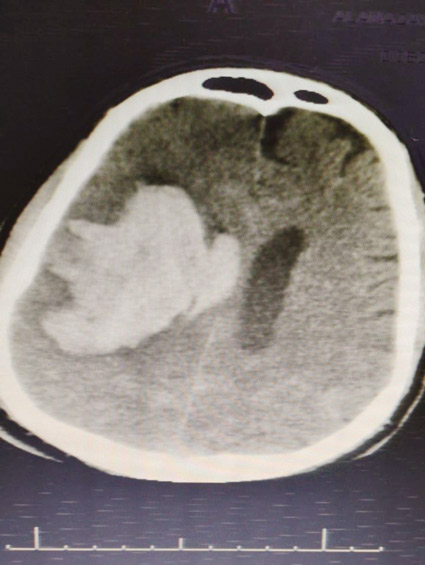

وأكد تجمع حائل الصحي أن الفريق الطبي استقبل الحالة عن طريق قسم الطوارئ وهو يعاني من تشنجات عصبية، وشلل في الجانب الأيسر من الجسم إثر تعرض لغيبوبة، وتم على الفور إجراء الفحوصات السريرية والمخبرية والأشعاعية التي أكدت وجود نزيف في المخ؛ بسبب التشوه الشرياني الوريدي الدماغي، مما تطلب على الفور إخضاع المريض وإجراء عملية جراحية فورية باستخدام الميكروسكوب الجراحي لاستئصال التشوه المسبب للنزيف الدماغي، تكللت -ولله الحمد- بالنجاح واستعاد المريض تحريك الجانب الأيسر بعد فترة المتابعة له من قبل الفريق الطبي في قسم التنويم بالمستشفى إلى أن خرج بالسلامة وبصحة جيدة.